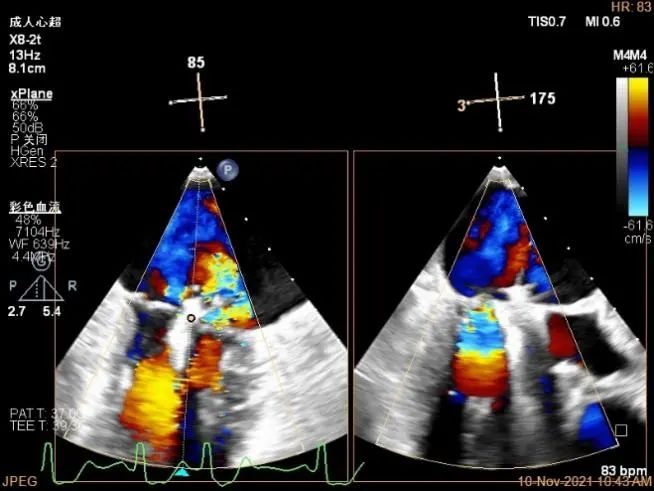

肺静脉血流频谱逐渐恢复正向

肺静脉血流频谱恢复正向

肺静脉血流频谱完全正向